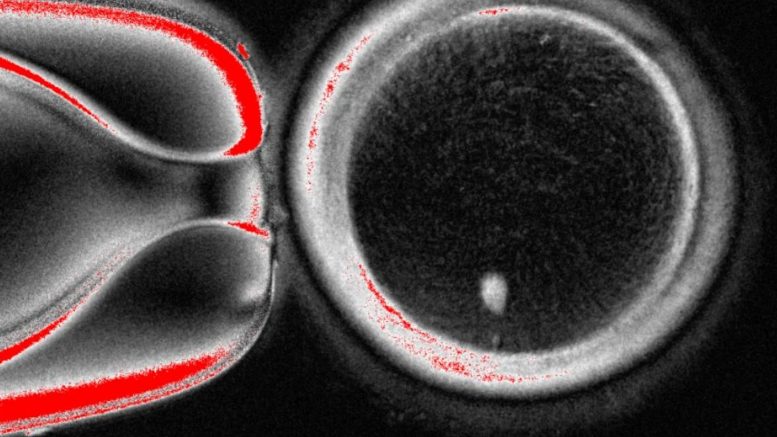

- El desafío:El proceso en humanos es complejo, ya que el ADN del óvulo normal y el núcleo del donante no pueden duplicarse al mismo tiempo.

- El avance:Para sortear este problema, los investigadores emplearon un método llamado «mitomeiosis», que fuerza al óvulo a dividirse y descartar un par de cromosomas, haciéndolo viable para la fertilización.

- Nuevo desarrollo:En el experimento más reciente, se crearon 82 óvulos funcionales, de los cuales un 9% se desarrolló hasta el estado de blastocisto